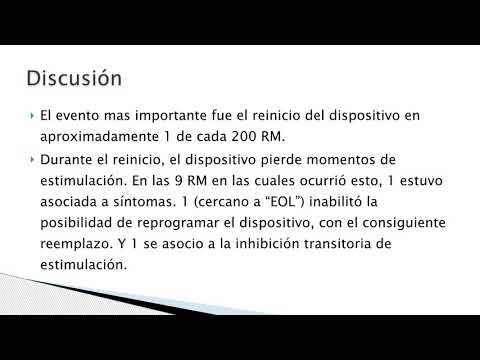

RNM y dispositivos. Dr. Mariano Napoli Llobera. Residencia de Cardiología. Hospital C. Argerich. Buenos Aires